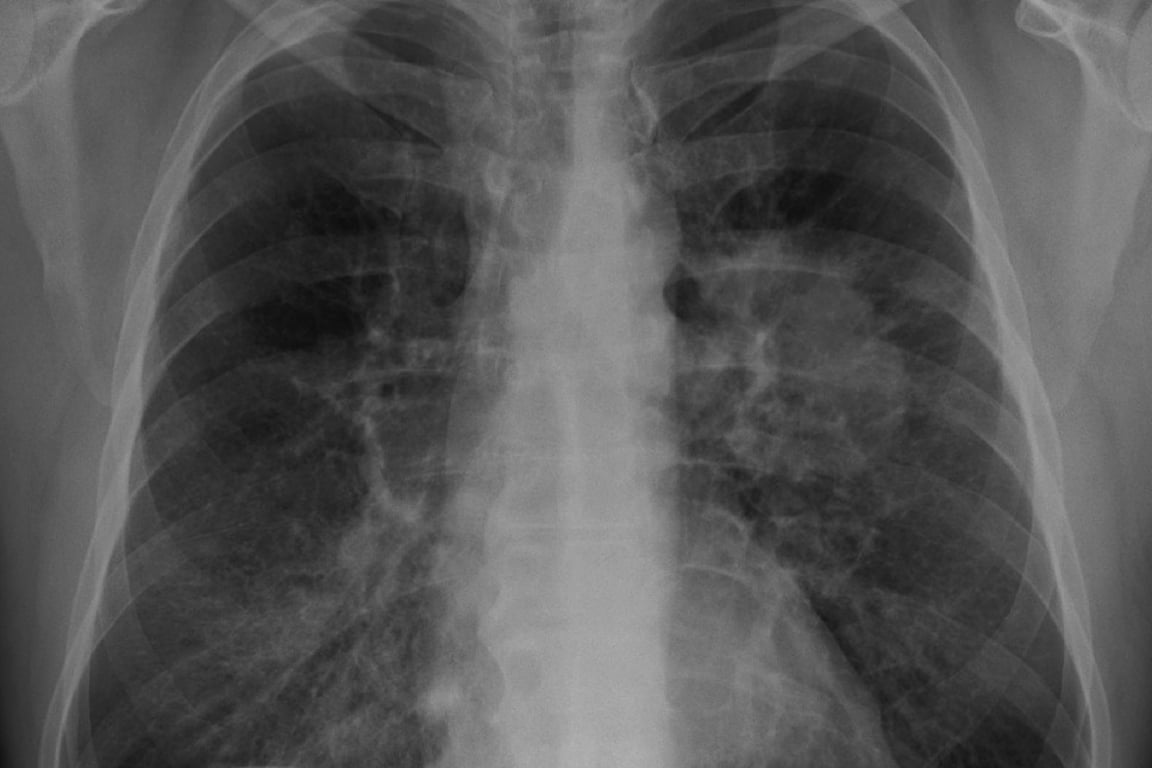

Nový výzkum v časopise Thorax zjistil, že lidé, kteří často jedí uzeniny, limonády a instantní jídla, mají až o 41 % vyšší riziko rakoviny plic.

Rakovina plic souvisí i s potravinami